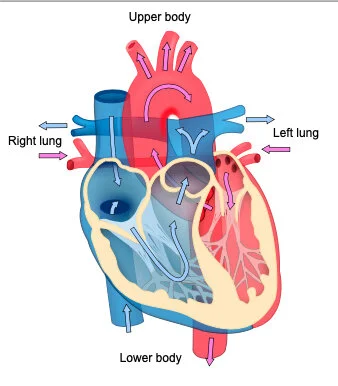

“William Harvey (1578-1657), who founded modern experimental physiology, was the first to establish not only the fact of the circulation but also the physical laws governing it, and is commonly reckoned the Father of Modern Medicine. He owed his interest in the movements of the blood to Fabricio, his tutor at Padua, who drew his attention to the valves in the veins, thus suggesting the idea of a *circular* as opposed to a to-and-fro motion. Harvey’s great generalisation, based upon a long series of experiments in vivo, gave the coup de grâce to Galenic physiology.

“Einthoven’s name is linked partly with the design of a physical instrument, the string galvanometer, partly with the so-called electrocardiogram, a record of the electrical potential fluctuations at the surface of the body, which accompany the heart beat. The heart beat, like the piston movement of a steam engine, is a cyclic process. Behind this process lies, in the first place, a similarly cyclic process in the heart muscle.

…

“The same mechanism governing the characteristics of the electrocardiogram, also governs the characteristics of the mechanical process during the heart beat. We should remember in this connection that the mechanical process not only consists of the succession of the stimulation of the separate parts of the heart compartments, but also of the cooperation of the individual parts of the heart wall which form the essential condition for the mechanical effect in the individual ventricle or in the individual auricle. A deficiency in this cooperation can, with regard to the mechanical effect, be as fatal as a valvular insufficiency. Today, the importance of the mechanism discovered by Einthoven can easily be realized.”

“The ancient world and the Middle Ages had no idea of the existence of the circulation of the blood. It was not until the Late Renaissance that efforts were made to grasp this process anatomically and understand its function. Thus, Miguel Serveto searched in vain for a connection between the right heart and the left, and in so doing discovered the lesser circulation in 1553. In 1569, Caesalpinus traced the path of the large circulation. Jacobus Sylvius (1543), Canani (1564), and Fabricius of Aquapendente (1574) concurred in recognizing the centripetal movement of the venous bloodstream from the structure and arrangement of valves in the veins. Before their time it had been believed that blood flowed outwards to the periphery, even in the veins.

“William Harvey, one of the most gifted pupils of Fabricius (1578-1657), combined all these individual findings with the results of his own research to form the general picture of what we today call the circulation of the blood. But even he had no clear idea of the circulation in the region of the capillaries. This section was explained and described for the first time by Malpighi in 1661, after he had viewed a frog's lung under a microscope.

“In any event, it is the year 1628, in which Harvey published his classic work De motu cordis et sangunis, that we can call the birth-year of cardiology.”